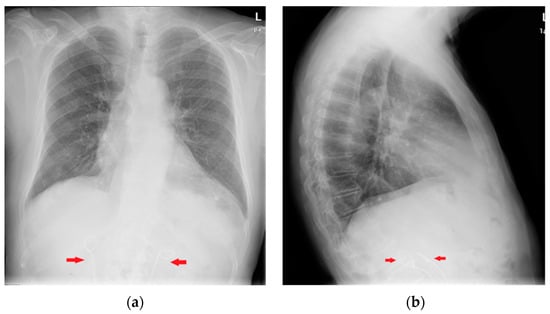

7. Chest Tubes

| Device | Most Frequent CXR-Detectable Anomalies and Complications |

|---|---|

| Chest tubes | Kinking Extrapleural/intrafissural/intraparenchymal/misposition Mediastinum juxtaposition Diaphragmatic trespassing Mediastinal invasion (uncommon) |